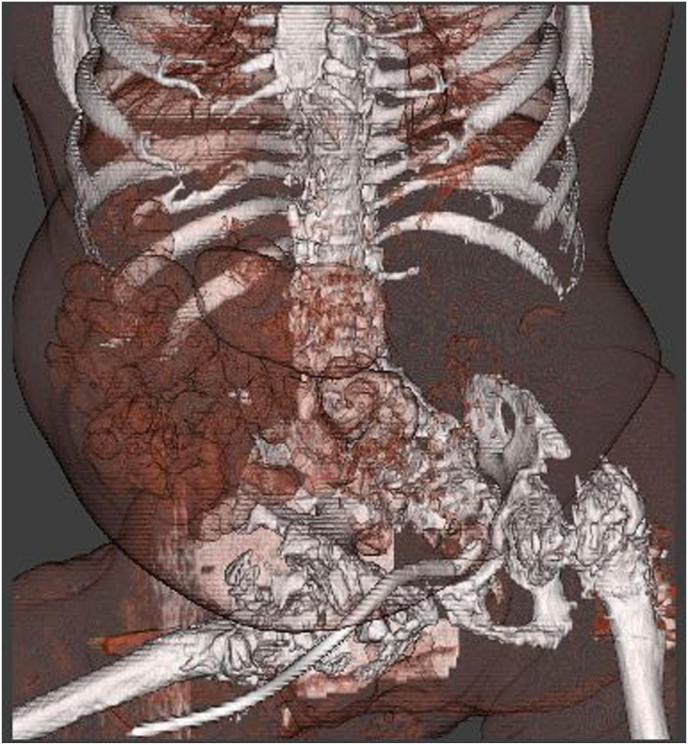

Obstruction of a ureter orifice by suprapubic catheter.

An Indwelling suprapubic catheter is an established solution for patients with meningomyelocele neurogenic bladder. We report on a case in which a routinely replaced suprapubic catheter obstructed the left ureter orifice. The catheter drainage holes were inside the distal left ureter which compromised urinary drainage from the other kidney as well. As a result, the patient suffered from acute renal failure. During his hospitalization, the catheter was replaced and re-located, and renal function rapidly improved. This case emphasizes that even procedures that have been routinely performed for decades can manifest with an unusual complications.

耻骨上留置导尿管是治疗脊髓脊膜膨出神经源性膀胱患者的一种成熟方法。我们报告了一例常规更换的耻骨上导尿管阻塞左输尿管口的病例。导尿管引流孔位于左输尿管远端内部,这也影响了对侧肾脏的尿液引流。结果,患者出现急性肾衰竭。住院期间,更换并重新放置了导尿管,肾功能迅速改善。该病例强调,即使是已常规进行数十年的操作也可能出现罕见并发症。